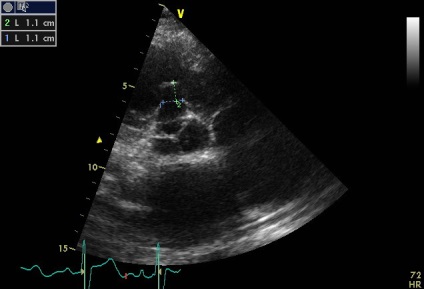

Bal kamra jobb kamra

Sinus Valsalva - egy zseb-szerű szerkezet határolt szálas gyűrűt szelepcsappantyú, és az illető semiiunaris aorta fal, annak felső határa - sino-csöves csatlakozás. A falakat a két szinusz van a szája, a jobb és a bal koroanrnyh artériák, és hívják a jobb és a bal koszorúér sinus, és a maradék egyharmad - a nem koszorúér. A beteg egy diszkontinuitás az aneurizma a jobb coronaria sinus Valsalva (ünnepelte gyakrabban), mint látható parastrenalnyh szakaszok rövid és hosszú távú (egy lejtőn) tengelyeken. Számos egyéb, kevésbé gyakori aneurizma orrmelléküregek, még kevésbé egyidejűleg 2 vagy 3 (nem tévesztendő össze egy egyszerű kiterjesztése aortagyök szintjén az orrmelléküregek, ellentétben, amelyek továbbra is legyen tarsoly alakú kiemelkedés a fal, mint a mi beteg). A formáció egy ilyen aneurizma egy patológiás állapottal vegyületet struktúrák bázis szelep szórólapok és aorta fal. Fistulák (kóros anasztomózis) a szinuszok szintet, és anélkül, aneurizma (pl, amely különféle fertőző endocarditis). Csakúgy, mint az aneurizma nem bonyolítja egy hosszú szünet (és általában nem, hogy klinikailag). A rés a kialakulását a sipoly kiváltható trauma, szívbelhártya-gyulladás, magas vérnyomás, stb de néha spontán. A szünet alakul súlyos volumen túlterhelés, olyan funkciókkal, hemodinamikus megnyilvánulások, attól függően, hogy melyik kamrában visszaáll az aortából. Ebben az esetben, a reset határozzuk meg a jobb kamrai kiáramlási traktus (2. típusú), egy jelentős növekedést véráramlást a bal kamrai kiáramlási traktus (disztálisan a sipoly, miközben a szisztémás keringésbe csökken). Drámaian megnövekedett a nyomás a jobb kamra (amint azt a gradiens tricuspidalis regurgitáció + jelei megnövekedett nyomás a jobb pitvarban). De pulmonális sávval egy reflexszerűen hipovolémia, amíg részlegesen „védett” (görcs) az ilyen akut volumen túlterhelés (fokozott jelei rezisztencia lehet számítani). A helyzet sürgető, és előírja szívsebészet.

áramoltassuk a jobb kamrai kiáramlási traktus (2-es típusú)